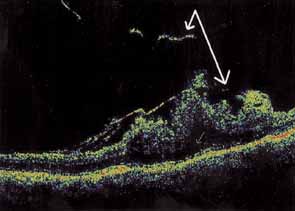

Some authors have commented on the importance of a posterior vitreous detachment in the pathogenesis of a macular hole.34,35 It is difficult to determine the vitreoretinal relationship preoperatively, even with careful slit-lamp evaluation. OCT testing can sometimes be helpful. However, the vitreomacular relationships are more accurately determined intraoperatively with use of oblique intraocular illumination and by noting the effect of gentle tractional forces on the macula during the vitrectomy. In some cases, what was thought to be a posterior vitreous separation preoperatively was actually found to be a large, optically empty space (Fig. 3).

Tissue surgically peeled from the macular region in cases of impending macular hole has been found to be clinically consistent with posterior hyaloid. This finding was supported by electron microscopic examination of the tissue (Fig. 4).13,36 This observation is supported by the work of Kishi and Shimizu.37 They noted a large, optically empty space that appeared to be a complete posterior vitreous detachment in eyes with advanced liquefaction of the vitreous. They termed this area the posterior precortical vitreous pocket (PPVP). They found this pocket in 48 of 84 eyes with either an incomplete or no posterior vitreous detachment, and in 19 of 36 eyes with a posterior vitreous detachment. They noted that in eyes with advanced liquefaction of the vitreous, a large PPVP appeared to be a complete posterior vitreous detachment. In all of their postmortem cases, the posterior layer of the PPVP was found to be a thin layer of cortical vitreous. The presence of this PPVP strengthens the hypothesis that contraction of remaining attached cortical vitreous causes tangential traction on the macula, which gives the clinical appearance of an idiopathic macular cyst or hole.13,25,26,38 These impending holes or cysts' have been noted to resolve with spontaneous or surgical stripping of the membranes.13,25